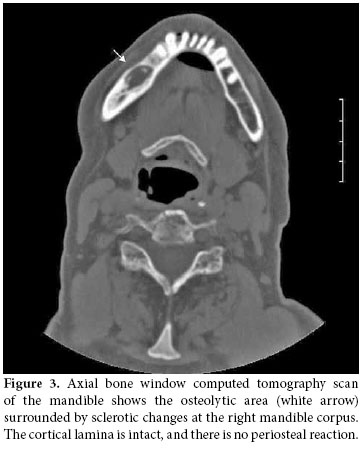

Together with the past history of long-term alendronate treatment and occurrence after tooth extraction, relevant clinical symptoms and conventional radiographic findings led to the suspicion of ONJ in this patient. We immediately ordered dental computed tomography (CT) which revealed sclerosis and osteolytic changes in the right mandible. This confirmed the diagnosis of osteonecrosis (Figures 2, 3). The patient also consulted with dental surgeons, and since there was no pathologic fracture, extra-oral fistulae, or osteolysis extending to the inferior border of the mandible, the disease was accepted to be in the second stage. Surgery was not recommended, and conservative management was started. The patient was advised to discontinue the alendronate treatment, and the etanercept treatment was also stopped. A good oral hygiene regimen using antibacterial tooth rinse was recommended. Her complaints and symptoms alleviated gradually. A control panoramic radiography taken after one year of bisphosphonate withdrawal displayed healing of the exposed bone (Figure 4).